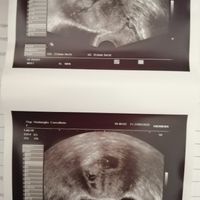

Oggi ho fatto il Gtest e tra dieci giorni circa oltre agli altri esami avrò il risultato anche del sesso, così un po’ per divertirci a sfatare miti volevo allegare 2 ecografie una di 8 settimane fatta...

Oggi ho fatto il Gtest e tra dieci giorni circa oltre agli altri esami avrò il risultato anche del sesso, così un po’ per divertirci a sfatare miti volevo allegare 2 ecografie una di 8 settimane fatta internamente e una di 11 (oggi) fatta...